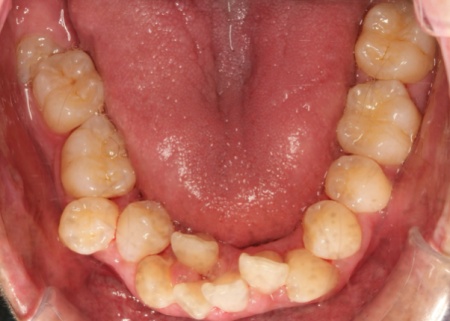

治療前

拝見したところ、全体的に歯並びがガタガタと乱れていました。

特に上下の前歯は正常な位置から大きくずれて重なり合って生えており、歯ブラシが当てにくく汚れが溜まりやすいため、歯ぐきの炎症や口臭の原因になっています。